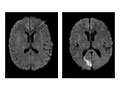

Magnetic resonance imaging (MRI) of the head

Normal:

All structures of the head—the brain, its vessels, spaces, nerves, and surrounding structures—are normal.

No abnormal growths, such as tumours, in or around the brain are present.

No bleeding, abnormal blood vessels (AV malformations), abnormal pockets of fluid, blockage in the flow of blood, or bulges in the blood vessels (aneurysm) are present.

No signs of infection or inflammatory disease, such as encephalitis or meningitis, are present.

Abnormal:

Tumours in the brain or in areas outside the brain, such as an acoustic neuroma, are present.

Bleeding or swelling (edema) in or around the brain is present.

Areas of infection or inflammatory disease, such as encephalitis or meningitis, are present.

Abnormal areas in the brain may mean that certain diseases, such as Huntington's disease, multiple sclerosis, Parkinson's disease, or Alzheimer's disease, are present.

Bulges or weak areas (aneurysms) or abnormal blood vessels (such as an AV malformation) are present.